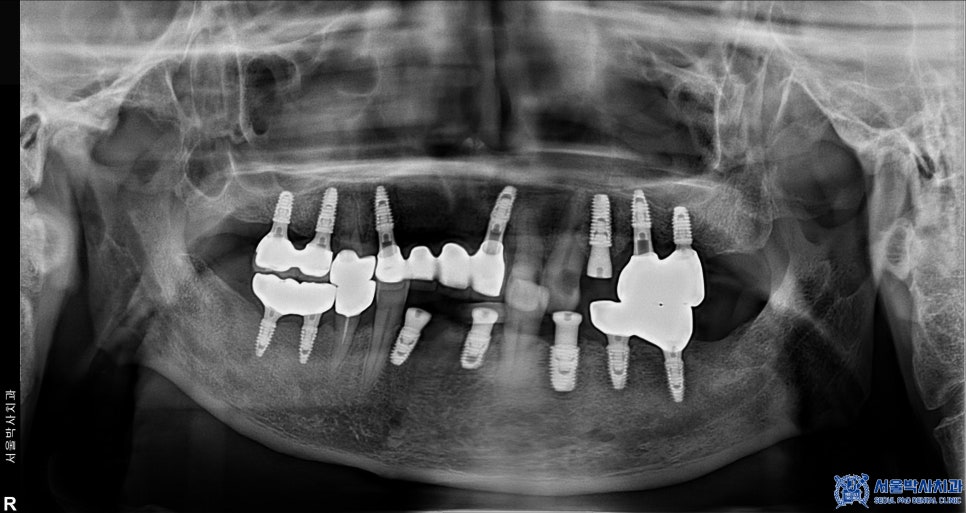

임플란트를 식립하기로 결정했고

앞니는 2개의 임플란트만 식립하여

브릿지로 연결하기로 하였습니다.

이때 임플란트를 안정적으로 고정하기 위해서는

충분한 골량이 필요하기 때문에

해당 부위에는 뼈이식을 함께 진행하기로 했습니다.

안정적으로 식립한 후에는

즉시 임시 치아를 장착해 드려

환자분이 치아가 없는 상태로 지내는

불편함을 줄여드렸습니다.